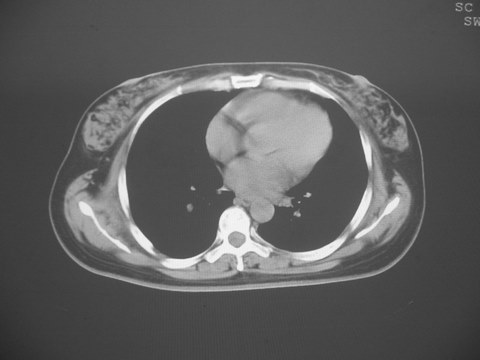

无意中发现右背部肩胛下缘半球状突起,无红,热,痛感觉。拍平片未见异常。ct发现右肩胛下角深层新月型软组织肿胀,ct值-50至15,大家看看是什么性质,来源,初步考虑来源于下后锯肿,考虑下后锯肌肿胀,可是病人无明确外伤史,也不疼痛

三、弹性纤维瘤影像

典型位于背部,在肩胛下角和胸壁软组织之间,肿瘤表面为菱形肌和背阔肌所被覆深部,紧邻肋骨和肋间肌,呈半圆形或扁豆状,宽基底与胸壁相交,边界比较清楚,相邻的肌肉和肋骨无侵蚀,部分病变与其表面的临近肌肉之间可受压呈弧形的脂肪界面,肿瘤周围软组织无水肿。

从mr表现可以推断ct影像,即肿块呈软组织密度,病灶内可出现脂肪密度的低密度影。

大家注意下 这个病人有乳腺增生,和肩胛下病变没什么关系,但ct下发现乳腺增生的好象不多,因为她有乳腺增生病史,所以才有所注意